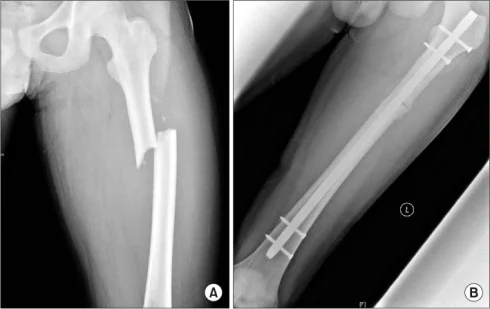

| Intramedullary Nails (IMN) | • Best fixation for diaphyseal long‑bone fractures – Femur, Tibia: preferred over plating • Locked IMN provide stable fixation | ![]() |